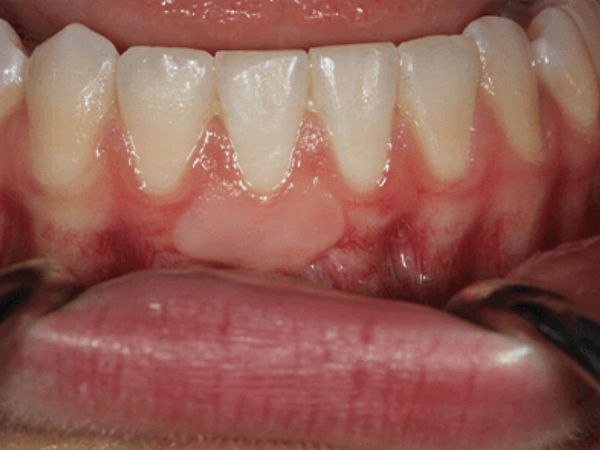

After